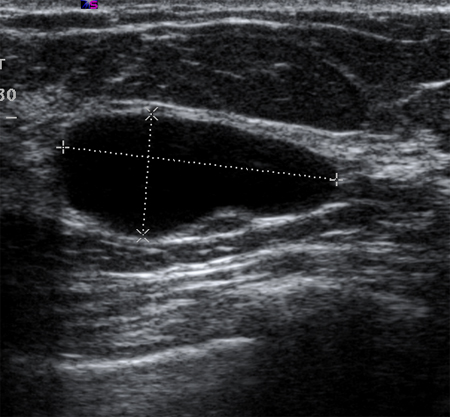

Imagen en ultrasonografía de un quiste simple

Cortesía del Dr. Lane Roland, University of Louisville; utilizada con autorización

Ver esta imagen en el contexto de la/s siguiente/s sección/es:

Evaluación de masas en la mama